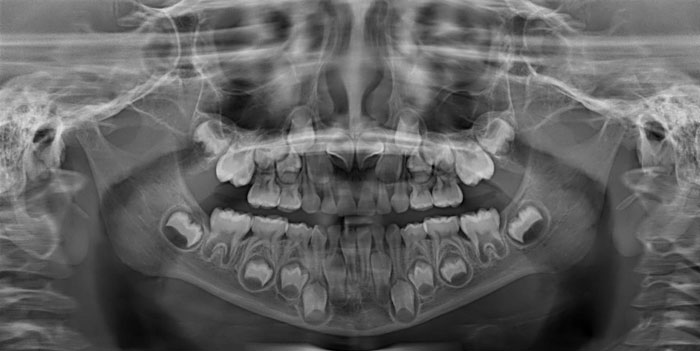

Panoramic X-Ray Of A Child (Adult Teeth Growing In)

Today I Took A Dental X-Ray For A Child. This Is How The Milk Teeth Change Permanently. The Picture Clearly Shows How The Premolar Comes Out

The Extra Row Of Teeth In The X-Ray Of My 7-Year-Old Kid